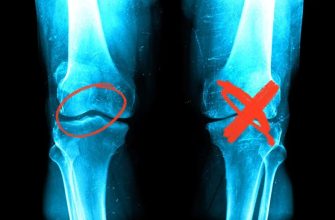

Joint hypermobility, also known as hypermobility syndrome

Joint immobility, also known as stiff joints or limited

Joint pain can be a debilitating condition that affects

Joint pain and swelling can be debilitating, causing

Joint pain is a common ailment that affects millions

Joint pain and stiffness can be incredibly frustrating

Joint stiffness and pain can be incredibly debilitating